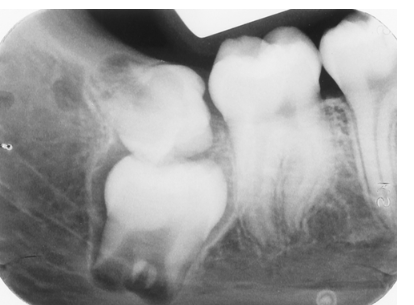

List the anomalies seen in this radiograph of the 3rd molar region.

Impacted 2nd molar and microdontic 3rd molar

Impacted 3rd molar and supernumerary 4th molar

Impacted 2nd molar; microdontic, impacted 3rd molar; and dilacerated mesial root of the 2nd molar

Impacted 3rd molar; impacted, supernumerary 4th molar; and dilacerated mesial root of the 2nd molar